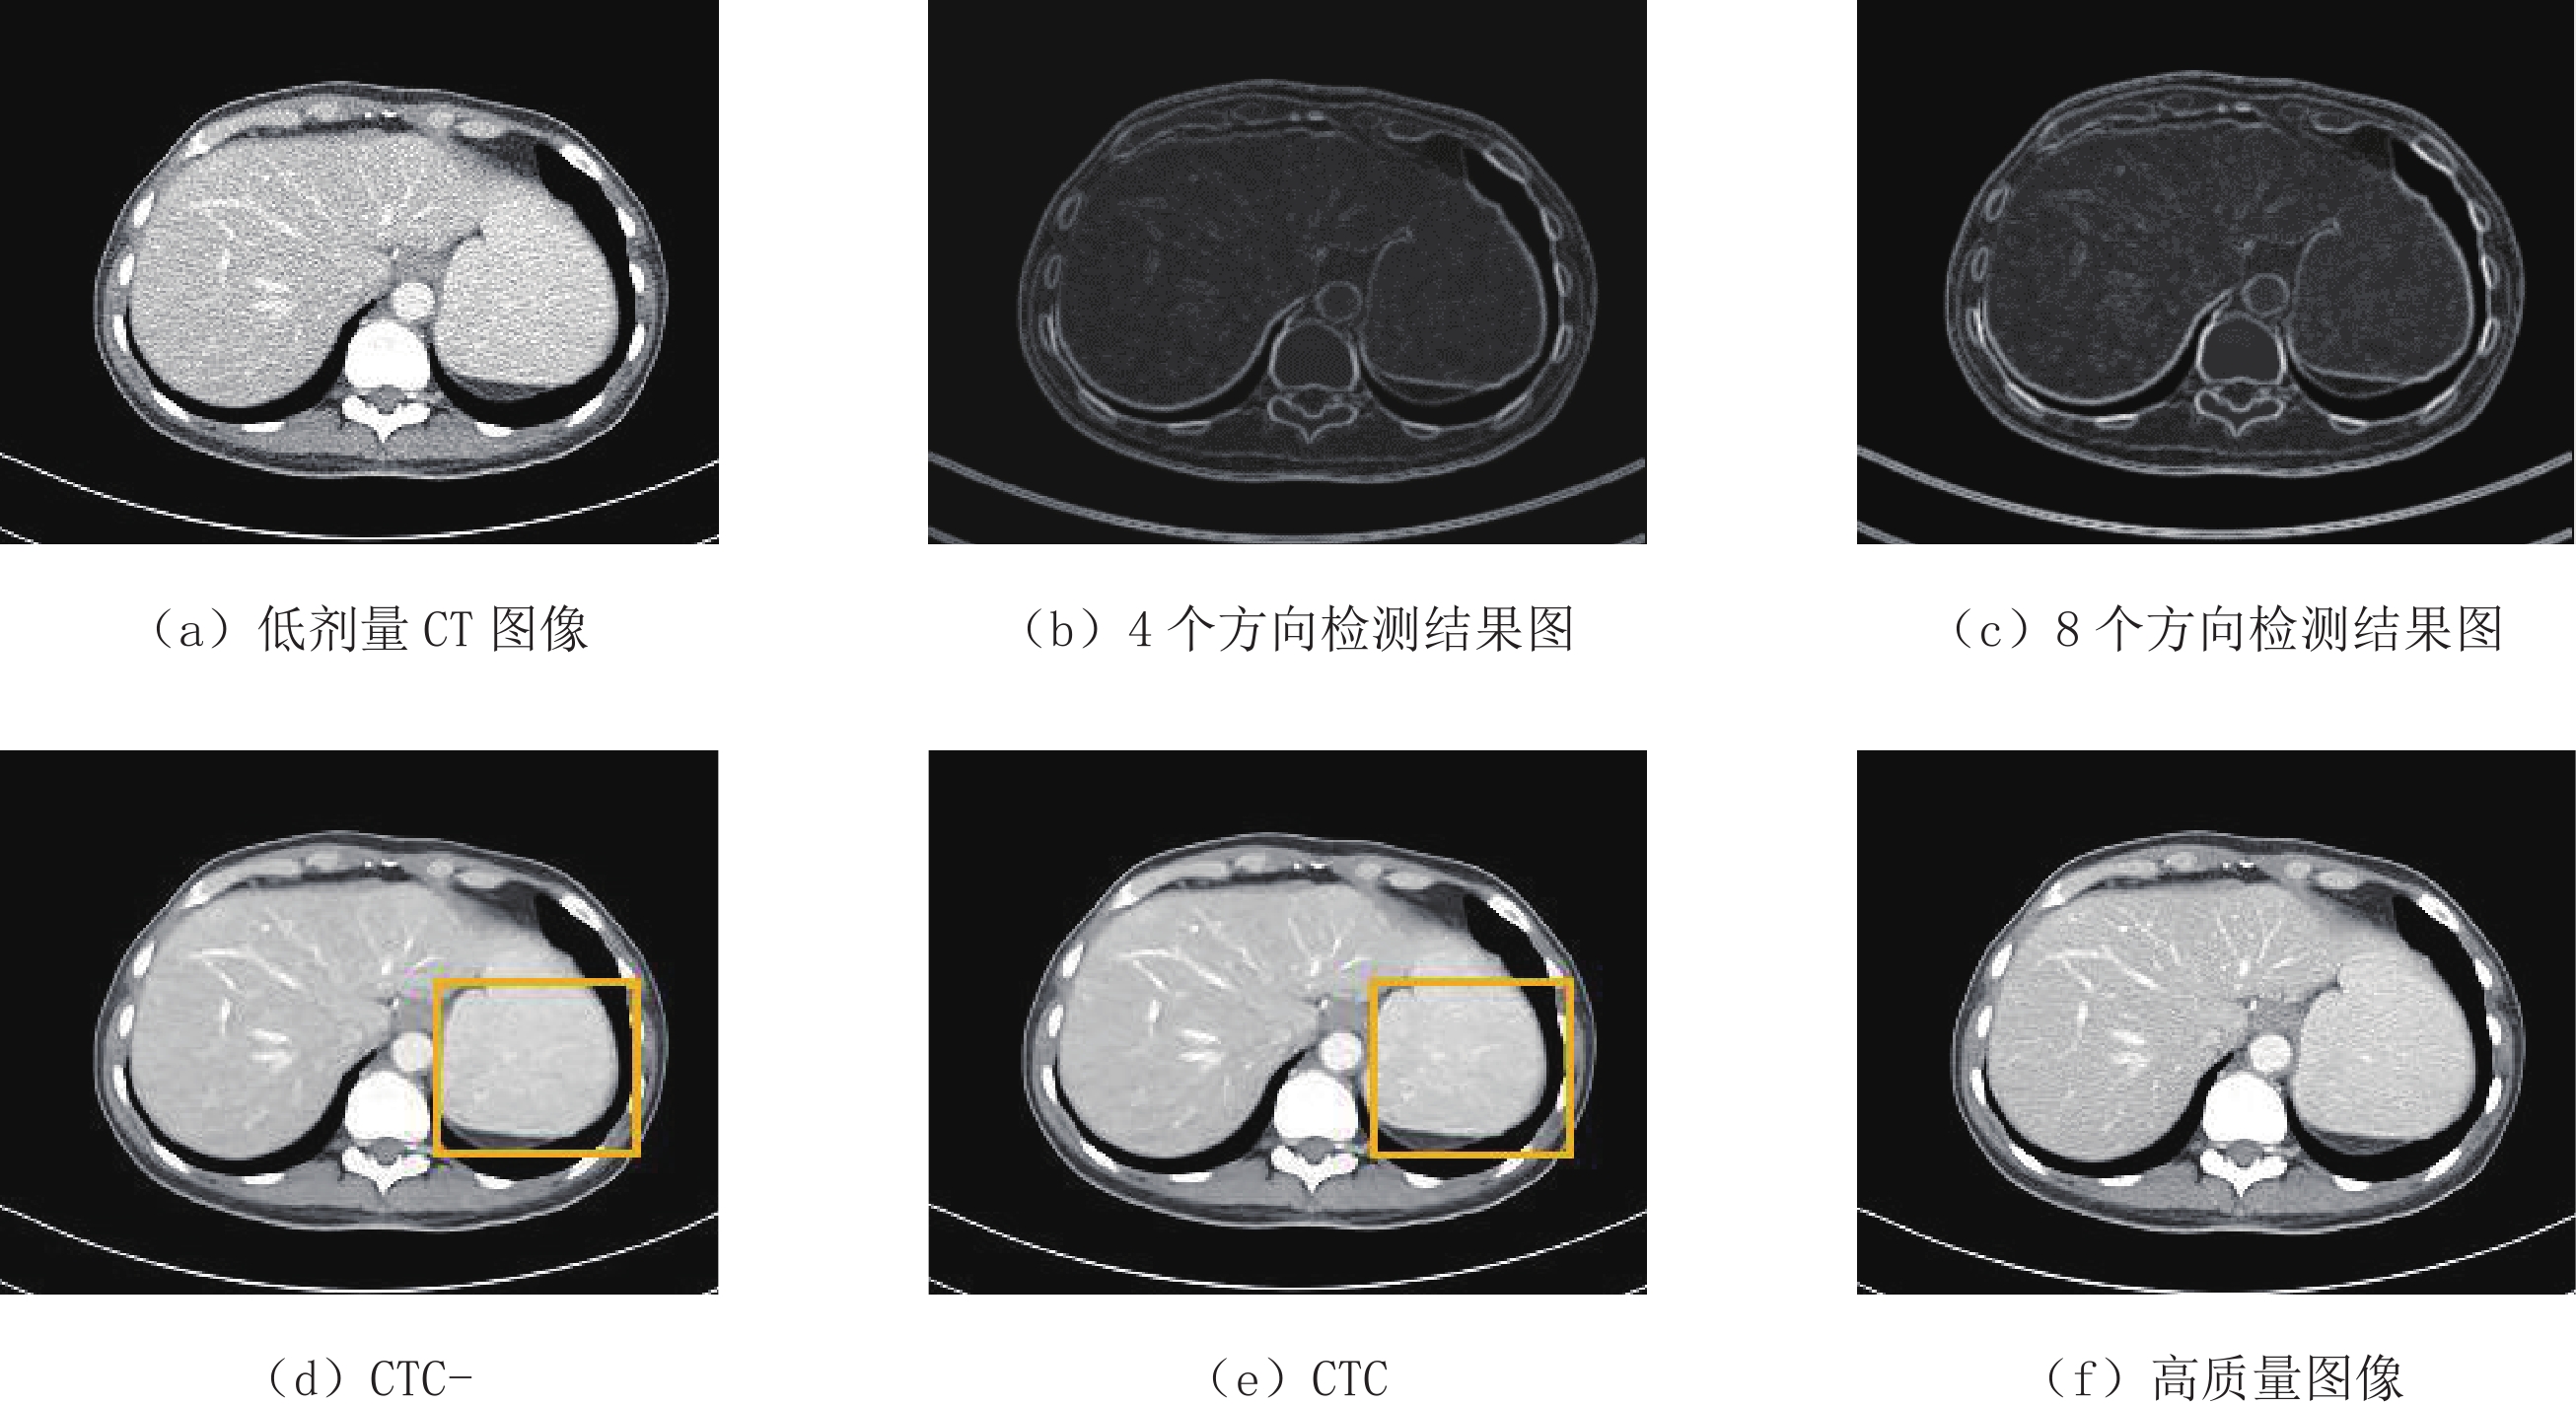

为了讨论CTC网络中图像边缘增强模块对其性能的影响,我们去除CTC网络中的图像边缘增强模块,将其标记为CTC-,并与CTC网络进行定量和定性分析,其结果如表2和图9所示。由表2可见,CTC网络模型的3项评估指标均优于CTC-,其中PSNR指标提升最为明显,表明CTC网络去噪效果更优。图9(e)与图9(d)对应的黄色区域显示CTC网络具有更好的性能,更完备的信息,更适合医学诊断。

表 2 图像边缘增强优化器的影响实验结果Table 2. Effect of image edge enhancement block on experimental results网络模型 评估指标 R S E CTC- 33.310 0.954 0.023 CTC 33.574 0.957 0.022 CTC网络模型中的图像边缘增强模块使用8个方向的索贝尔算子,我们对0°、90°、180°、270° 4个方向的索贝尔算子进行实验与比较。实验结果如图9所示,对于腹部低剂量CT图像,图9(c)中8个方向的索贝尔算子比图9(b)中4个方向的索贝尔算子呈现更多的细节信息,所以我们使用8个方向的索贝尔算子作为图像边缘增强模块。